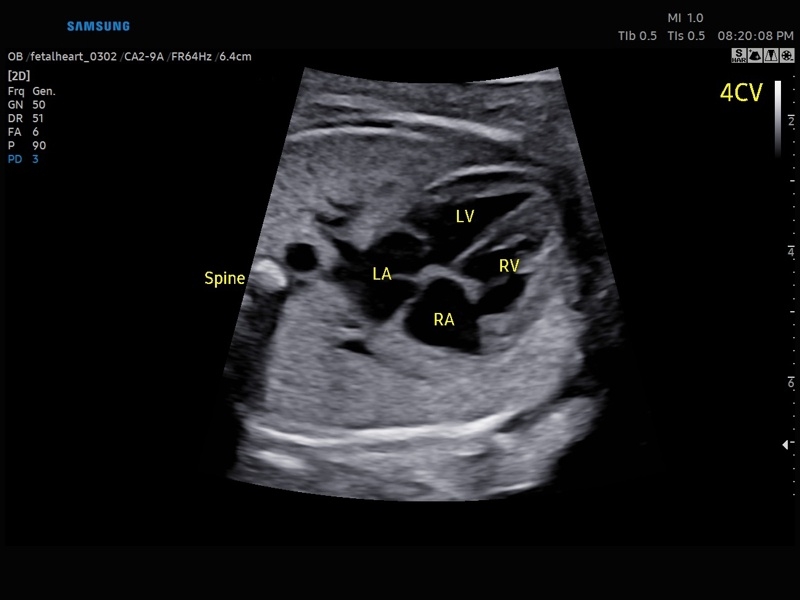

• Сердце плода:измерения в В-режиме (отношение площади сердца и грудной клетки), измерения в М-режиме (толщина межжелудочковой перегородки в диастолу, конечнодиастолический размер левого желудочка, толщина задней стенки левого желудочка в диастолу, толщина межжелудочковой перегородки в систолу, размер левого желудочка в систолу, толщина задней стенки левого желудочка в систолу, внутренний размер правого желудочка в диастолу), измерения в режиме спектрального допплера (легочный ствол, артериальный проток, нижняя полая вена, венозный проток, восходящая аорта, нисходящая аорта, трансмитральный кровоток, митральная регургитация, трикуспидальный кровоток, трикуспидальная регургитация, индекс преднагрузки, ЧСС).

• МодульSTIC- объемная динамическая визуализация сердца плода.

• Акушерство и гинекология

• Кардиология